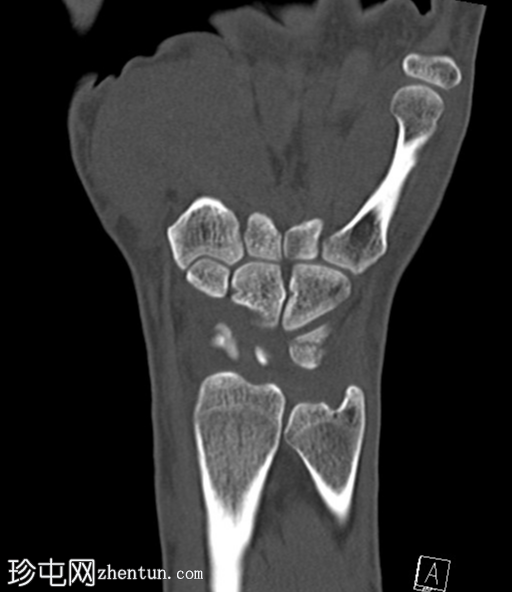

CT

冠状位片

平扫

CT轴位、矢状位和冠状位片显示三角骨背侧粉碎性撕脱性骨折。

未见其他骨折。